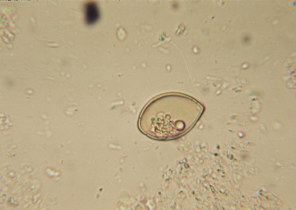

Capillaria aerophila (яйцо)

| Цикл | Взрослый червь живёт в бронхах ежа. Выход яиц осуществляется с калом ежа, личики развиваются в яйцах. Ёж инфицируется посредством прямого попадания яиц внутрь или посредством поедания переносчиков яиц (дождевых червей). |

| Симптомы | Аналогичны симптомам при Crenosoma striatum (часто также встречается смешанное инфицирование обоими видами лёгочных гельминтов). |

| Диагноз | Яйца в кале |

| Терапия | Флубендазол (средство на выбор), фенбендазол. Антибиотики при бактериальной вторичной инфекции, муколитика, замена жидкостей. |